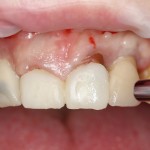

Для удаления зубов мы используем прямой элеватор и тонкие «корневые» щипцы-байонеты. Сама процедура удаления занимает около 10 минут:

Давайте внимательно посмотрим на состояние лунок центральных резцов после удаления:

Приемлемый фенотип (сочетание толщины и ширины участка жевательной десны) — это, конечно, приятно. Но гораздо важнее сосредоточиться на рисках, их на этот момент два:

— травматическое повреждение слизистой, вызванное удаление зубов связано с тем, что при хроническом воспалении слизистая оболочка теряет эластичность, поэтому легко рвётся. Такая ситуация создаёт серьёзную угрозу эстетическому результату лечения, в зависимости от того, насколько быстро десна придёт в норму.

— как и предполагалось после КЛКТ, утрата костной стенки привела к тому, что десна провалилась в просвет лунки левого центрального резца. Это еще больше усугубляет клиническую ситуацию.